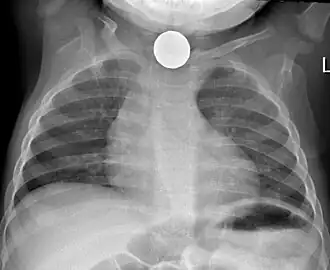

Foreign body aspiration

Chest x-ray in an infant showing aspiration of a metallic coin without signs of mediastinal shift.

Foreign body aspiration is a major cause of death in young children due to their underdeveloped swallowing coordination. Young children most commonly ingest toys, coins, or food.[21] On chest x-ray, the most frequent sign is air trapping that can lead to a mediastinal shift. Atelectasis and pneumothorax may also occur in the setting of foreign body aspiration. The diagnosis is made in conjunction with clinical symptoms and confirmed and treated with bronchoscopy.[22]